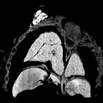

Caption Play MovieSerial 2D ECM image stack in the coronal plane of mutant (E17.5) reveals double outlet right ventricle (DORV) of the Tetralogy of Fallot subtype with pulmonary atresia and subaortic VSD.

Copyright This image is from the Laboratory of Dr. Cecilia Lo, a member of the Cardiovascular Development Consortium (CvDC), Bench to Bassinet (B2B) program of the National Heart Lung and Blood Institute (NHLBI), and is displayed with the permission of the authors. J:175213